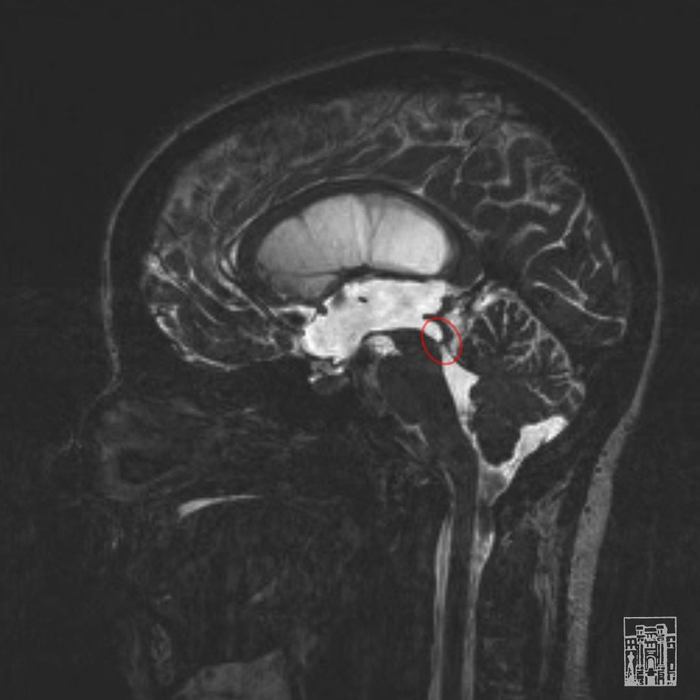

У малыша стремительно развивались сразу несколько патологий центральной нервной системы, одно из них – гидроцефалия. Избыточное накопление спинномозговой жидкости в мозге разрушало его и увеличивало голову в размерах.